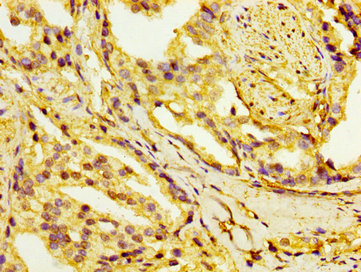

IHC image of CSB-PA010766LA01HU diluted at 1:100 and staining in paraffin-embedded human prostate cancer performed on a Leica BondTM system. After dewaxing and hydration, antigen retrieval was mediated by high pressure in a citrate buffer (pH 6.0). Section was blocked with 10% normal goat serum 30min at RT. Then primary antibody (1% BSA) was incubated at 4°C overnight. The primary is detected by a biotinylated secondary antibody and visualized using an HRP conjugated SP system.